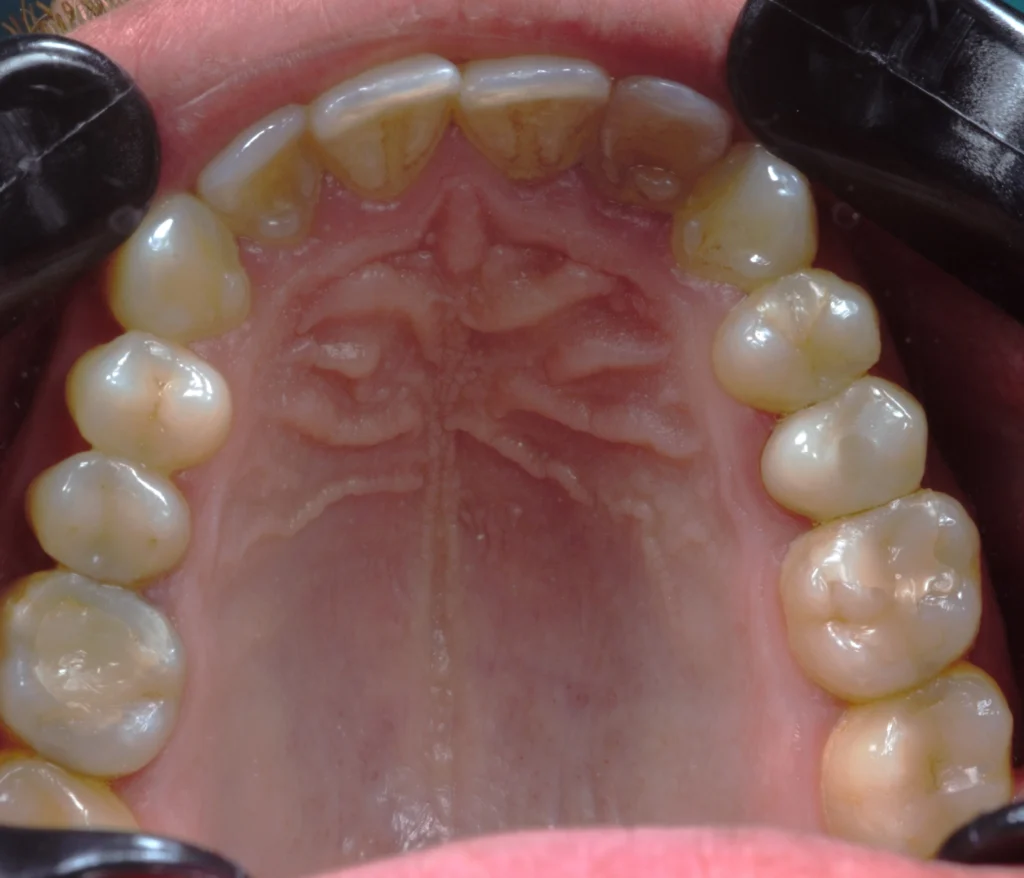

After a healing period of six months, the implant achieved excellent osseointegration. At this stage, we proceeded with the final restoration phase, ensuring everything was perfectly stable and ready.

We delivered a high-quality, screw-retained zirconia crown that blends seamlessly with the natural teeth. The result is a subtle yet powerful transformation—a small change that made a big difference in the patient’s smile and confidence.Â